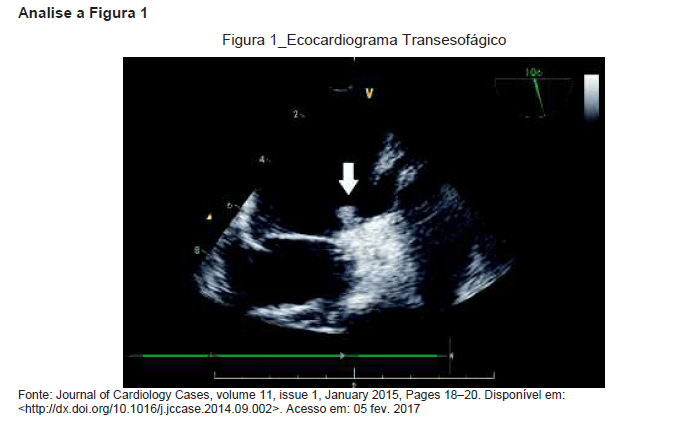

Homem de 46 anos, assintomático, foi admitido no hospital com hemiplegia e afasia. Nega cardiopatias, história de arritmias ou outros sintomas neurológicos. Nega tabagismo. O eco transtorácico revelou câmaras cardíacas com dimensões normais. Realizou ecocardiograma transesofágico.

De acordo com a imagem apresentada na figura 1, a principal possibilidade diagnóstica para esse caso é